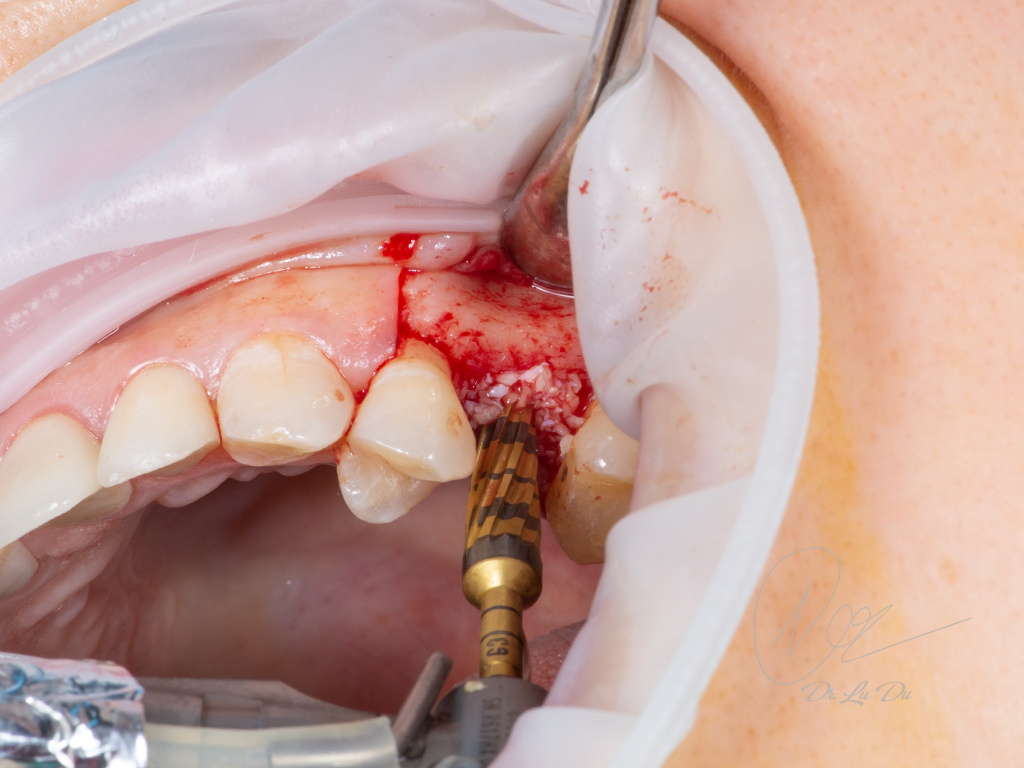

Имплантация AnyRidge с двусторонним закрытым синус-лифтингом.

Осложнения: правосторонний гайморит.

Кейс MINEC: Dr Lu Du